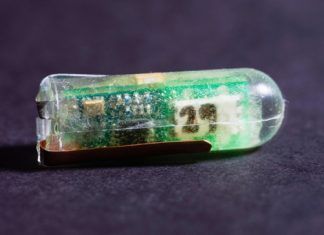

Energía gracias a pequeños sensores que pueden consumirse

Suministro de energía gracias a los ácidos estomacales. Un grupo de científicos provenientes del Instituto Tecnológico de Massachusetts (MIT) y del Brigham and Women’s...